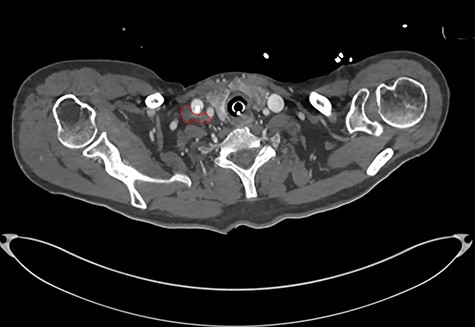

On diagnosing the right VCP, the original trauma series was reviewed by a consultant radiologist who identified a haematoma of the right carotid sheath in the neck (Fig. 1). A second CT scan of the neck and thorax was performed to determine the cause of the VCP 20 days after admission. This did not show a cause for the VCP but did demonstrate resolution of the haematoma (Fig. 2). A second FNE demonstrated resolution of the VCP 29 days following admission.

CT showing haematoma in the right carotid sheath following insertion of central line.